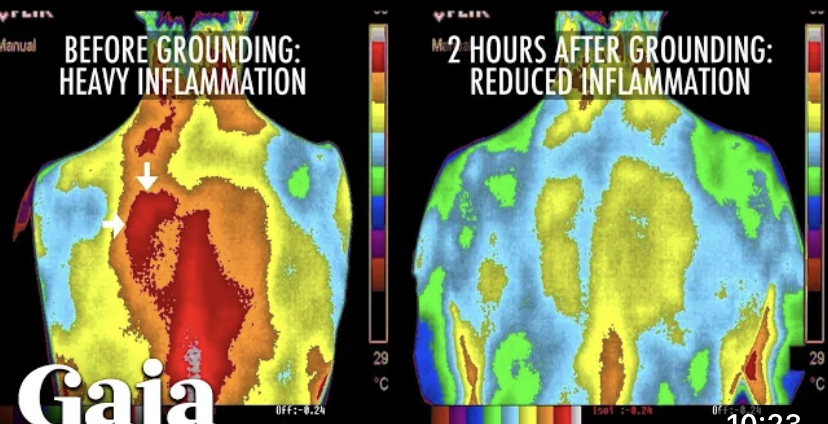

☀️ Împământarea este deci echivalentul mersului desculţ pe pământ, prin iarba. Este o metodă de energizare a corpului care este la îndemâna oricui şi nu costă nici nimic. Reprezintă conectarea corpului la câmpul energetic al Pământului, corpul nostru fiind şi el format din energie, minerale şi apă, asta traducându-se prin faptul că este un conducător de electroni. Aceşti electroni pe care îi contine Pământul, atunci când umblăm desculţi, ajung în corpul nostru. Fiind aprope tot timpul expuşi la radiaţii, corpul nostru dezvoltă electroni pozitivi care formează radicalii liberi. Când intrăm în contact direct cu Pământul, acesta acţionează ca o sarcină negativă, anulând electronii pozitivi.

☀️ Experţii spun că împământarea modifică activitatea la nivelul creierului, ajută corpul să se vindece mai uşor şi mai rapid, reduce stresul, scade nivelul de glucoză din sânge, creşte imunitatea, îmbunătăţeşte digestia şi calitatea somnului.

☀️ Totodată s-a demonstrat că mersul în picioarele goale prin iarbă îi poate ajuta pe cei care suferă de boli cronice, reducându-le durerile.

Sursă photo: Gaia